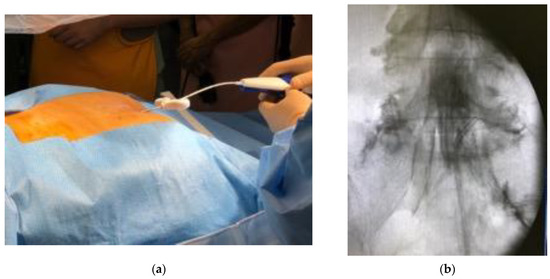

A multicenter retrospective analysis from seven facilities was conducted. TSCP was performed in the patients who suffered from chronic low back pain and leg pain due to lumbar spinal disorders. Contraindications are coagulation abnormality, pregnancy, contrast allergy, infections or tumor in the spinal lesion. The patient was placed in a prone position. Vital signs, including electrocardiogram, blood pressure and pulse oximeter were monitored. After local anesthesia was given around the sacral hiatus, the introducer was placed into sacral canal through the sacral hiatus under fluoroscopic guidance, then the epidural access catheter was inserted through the introducer after the removal of the inner cylinder (Figure 1a). A Racz catheter (BREVI-XL™, Epimed International Inc., Dallas, TX, USA) or epiduroscopy catheter (myeloCath®, Biomedica Healthcare Ltd., Tokyo, Japan) was used as an epidural access catheter (Figure 2). Contrast dye was injected into the epidural space in order to confirm the exact epidural placement of the catheter, and to identify any filling defects suggestive of a pathological lesion with epidural adhesion (Figure 1b). After a catheter was placed in the epidural space, an adhesiolysis was carried out by both moving the catheter for mechanical lysis and injecting normal saline for liquid lysis. Then, a mixture of steroid and lidocaine/bupivacaine was injected. Visual Analog Scales (VAS) for low back pain and leg pain were evaluated preoperatively, immediately postoperatively, and 1 month, 3 months and 6 months postoperatively. Perioperative complications were also assessed.

Figure 1. Procedure of trans-sacral canal plasty (TSCP). (a) The patient was placed in a prone position, and a local anesthesia was given around the sacral hiatus. The introducer was placed into sacral canal through the sacral hiatus under fluoroscopic guidance. The epidural access catheter was inserted through the introducer after removal of the inner cylinder. (b) Contrast dye was injected into epidural space in order to confirm exact epidural placement of the catheter, and to identify any filling defects suggestive of pathological lesion with epidural adhesion. After a catheter was placed at lesion site, an adhesiolysis was carried out by both moving the catheter for mechanical lysis and injecting normal saline for liquid lysis.